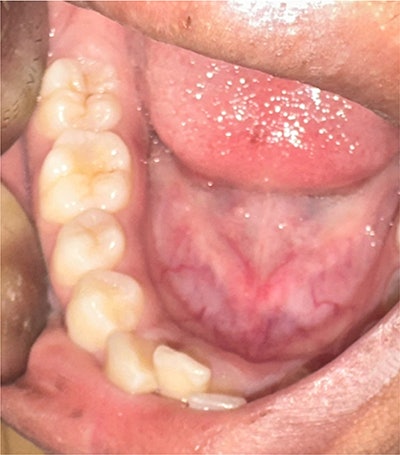

The intraoral photograph shows composite restoration of the mandibular right first molar. Images and captions courtesy of Chawla et al. Licensed under CC BY 4.0.